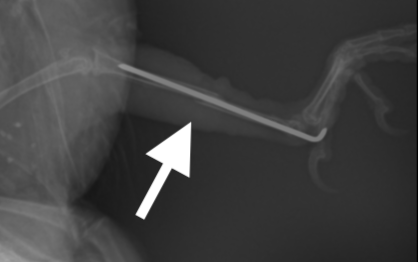

最後に踵部から出ているピンを折り曲げ、適切な長さにカットし、テーピングをして手術は終了です。

出血もほとんどなく、術後の経過も良好で、数日後退院しました。